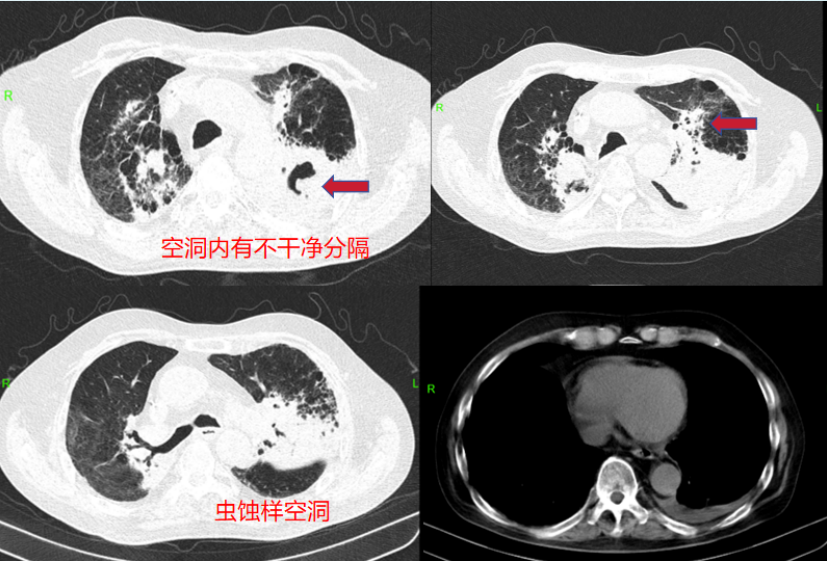

2023823日,患者氧合改善不明显。胸部CT:双肺见多发斑点、斑片及索条状病灶,边缘模糊,较前增多,部分呈网格状改变,部分实变(图2)。考虑新冠病毒肺炎(重型)。予俯卧位氧疗,甲泼尼龙40 mg抗炎平喘+依诺肝素0.4 ml qd预防性抗凝,胸腺法新免疫调节。

2  复查胸部CT(2023-08-23)

2023921日,患者于我院门诊复诊,日常活动可,近1周咳嗽咳痰加重,咳嗽时伴前胸牵扯痛。胸部CT示: 左肺新发感染病灶并膨胀不全; 左肺上叶范围甚大, 病灶边界隐约可辨, 密度不均, 多空洞, 部分呈虫蚀样或分隔样改变, 未见明显液平; 病灶间多结节影, 未见典型气囊影; 左侧胸腔少量积液, 胸膜轻度增厚(图4)

4  随访胸部CT(2023-09-21)